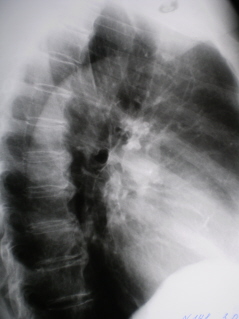

Иллюстрация 3. Рентгенограмма в боковой проекции.

Илл.  4,  5,  6 – срез 12 см. – фокусная тень неоднородной структуры, с не правильной формы просветлением в нижней части, с неровными, нечеткими контурами, с отдельными спикулообразными структурами по контуру. По медиальному контуру дифференцируется «вырезка» Риглера. От фокусной тени чётко дифференцируется «дорожка» к корню правого лёгкого. В корне гиперплазированные бронхо-пульмональные лимфатические узлы.

Илл. 7,  8,  9 – фокусная тень с эксцентрически расположенной, не правильной формы полостью распада, с неровными, с тенденцией к полицикличностью контурами.